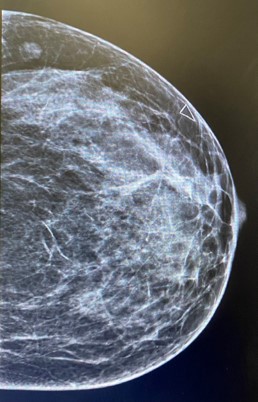

Figure 2: Left mammographic views CC of the left breast showing an irregular, spiculated, high-density mass in the upper outer quadrant. The lesion causes architectural distortion without associated calcifications. Findings are consistent with desmoid-type fibromatosis confirmed on histology.

Mammography presents irregular walled and highly dense lesion with no calcifications mimicking sometimes breast carcinoma [6].

Radiologic evaluation of our case revealed soft tissue mass inducing architectural distortion.